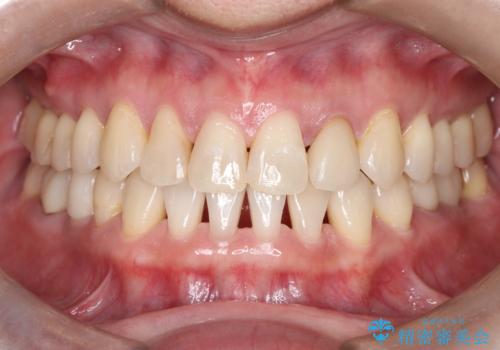

閉院による転院からのリカバリー。インビザラインからワイヤー矯正への切り替え